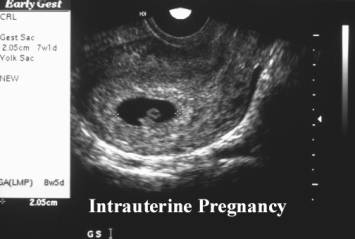

- Heterotopic gestations

describe the presence of both intrauterine and extrauterine gestations.

- Sonographic demonstration of

a normal intrauterine pregnancy is therefore not sufficient in either

symptomatic or asymptomatic patients especially after assisted

reproductive technology (ART). The adnexal and cul-de-sac should be

thoroughly assessed.